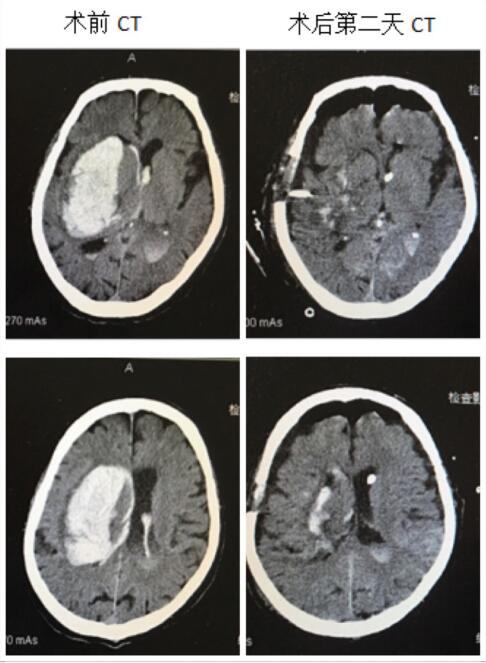

神经内镜手术治疗脑出血